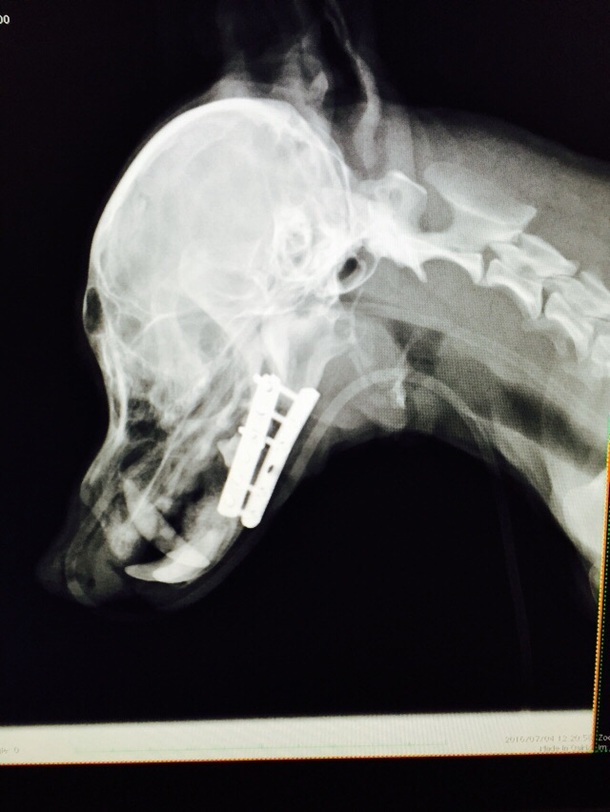

ココちゃんの現状ですが‥無事、9日土曜日に退院出来ました。 大手術本当に、頑張りました‼︎

これから、3ヶ月ほどのリハビリ療養になります。 今までのどれくらいの期間か‥開きっぱなしだった口は、舌が乾燥して萎縮して上手く使えません。 今は、赤ちゃんのように食べ散らかしてますが‥少しずつ、新しいお口での食べ方、使い方に慣れるよう、ココちゃんも懸命にリハビリ頑張ってます。

おかげさまで食欲もあり、術後の経過も今のところ良好です。 取り急ぎ、ココちゃんの経過報告になります。